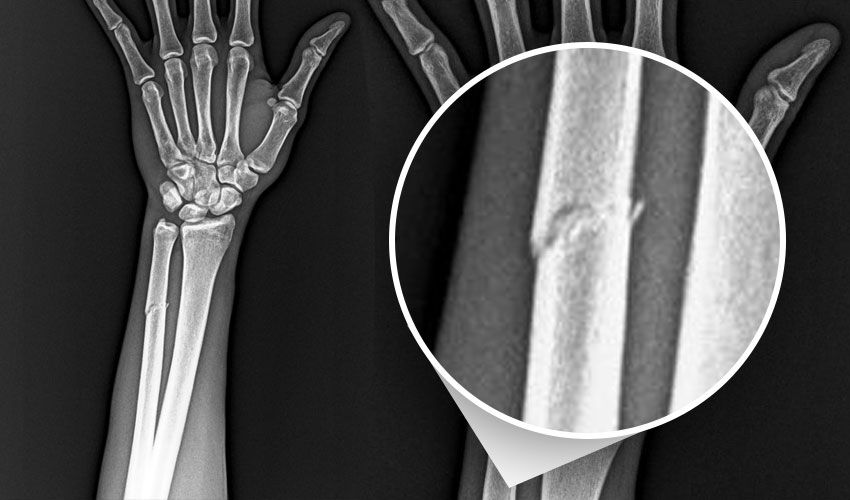

Mücadelede sakatlanan Nijeryalı golcünün kolunda kırık tespit edildi.

Beşir, "Futbol A Takımımızın RAMS Başakşehir ile oynadığı karşılaşma esnasında sakatlanarak oyundan çıkan futbolcumuz Paul Onuachu’nun yapılan muayenesinde sol kasık bölgesinde kas (adduktor kas grubu) yaralanması ve sol önkolda darbeye bağlı ayrışmamış kemik (ulna) kırığı tespit edilmiştir. Oyuncumuzun tedavisine sağlık ekibimizce başlanılmıştır" dedi.

"Paul Onuachu’nun yapılan muayenesinde sol kasık bölgesinde kas (adduktor kas grubu) yaralanması ve sol önkolda darbeye bağlı ayrışmamış kemik (ulna) kırığı tespit edilmiştir. Oluşan kırık sebebiyle oyuncumuza en az 6 haftalık tedavi programı uygulanacaktır."

Bordo mavili kulüpten yapılan paylaşımda, Onuachu'nun rakibiyle girdiği mücadelenin görüntülerine yer verilirken, "VAR’da göremediğiniz pozisyonun röntgen görüntüsü. Adaletiniz batsın." ifadeleri kullanıldı. Videonun sonunda ise Nijeryalı futbolcunun kırılan kolunun röntgen görüntüsü yer aldı.